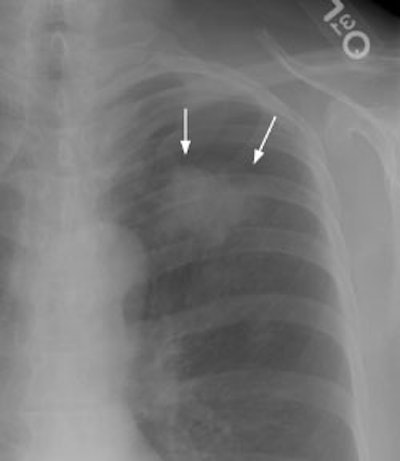

New Criterion for Determination of Pathologic Hilar Adenopathy

Example 1: This is an example of an N1 node in a patient with a lingular adenocarcinoma (left image). Although not pathologic by short axis size criteria, the lymphatic tissue in the left hilum has a convex border with the adjacent lung (white arrows). This node contained adenocarcinoma at histopathologic analysis. Some authors advocate using the presence of a convex margin of the interstitium with the lung parenchyma to indicate pathologic adenopathy to improve the sensitivity of CT for detecting hilar metastases [36].

Example 2: This patient is an example of a false negative CT for hilar nodal metastases even when applying the suggested new criterion. The patient had a peripheral adenocarcinoma in the left upper lobe (black arrows). The left hilar node (yellow arrows) is not pathologic by size criteria, nor does it exhibit a convex margin with the adjacent lung parenchyma. This is a normal node by CT, however, at histopathologic analysis the node was positive for malignant cells.